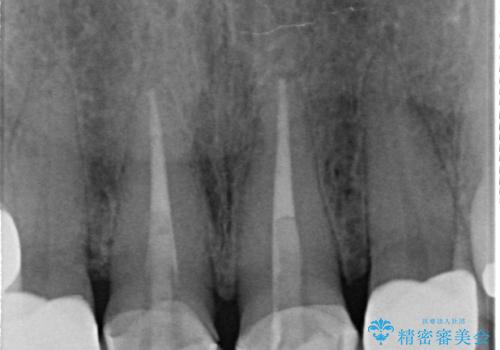

- 上顎の前から2番目の歯の古い樹脂をセラミックにしたいといらっしゃった方の症例です。

古い樹脂を除去後、オールセラミッククラウンによる補綴を行いました。

今回用いたオールセラミッククラウンはジルコニアフレームという白い素材の上にセラミックを盛っているため、審美性が非常に高いのが特徴です。

また、ジルコニアは人工ダイヤモンドの材料にも使われているほど高い強度を持っており、そのためオールセラミッククラウンは審美性だけでなく、奥歯やブリッジの補綴も可能とするクラウンです。